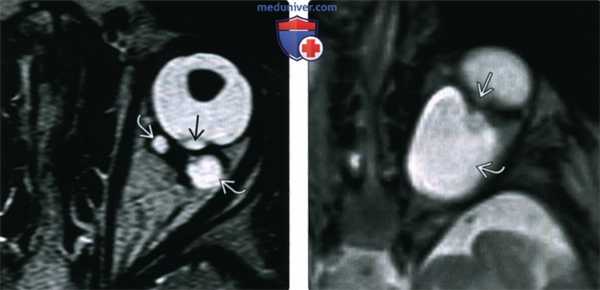

(Слева) У пациента с синдромом Айкарди при МРТ в режиме STIR в аксиальной проекции у места прикрепления зрительного нерва левого глаза определяется умеренного размера колобома. Также определяется крупная киста хориоидального сплетения, часто выявляемая у пациентов с этим Х-сцепленным синдромом.

(Справа) У пациента с синдромом CHARGE при КТ с КУ в аксиальной проекции определяется мелкий дефект заднего полюса правого глаза с локальным выпячиванием стекловидного тела. Также наблюдаются правосторонний микрофтальм и аномалия хрусталика.

3. МРТ при колобоме:

• Т1 ВИ и Т2 ВИ:

о Изоинтенсивна по сравнению со стекловидным телом

о При отслойке сетчатки - неоднородный сигнал, в том числе от геморрагической и богатой белком субретинальной жидкости (гиперинтенсивной при Т1)

о Глиальный пучок в центре аномалии типа «утреннего сияния» изоинтенсивный по сравнению с белым веществом

• Контрастирование:

о Склера контрастируется; может контрастироваться глиальный пучок при аномалии типа «утреннего сияния»

о Других контрастных патологических структур в дефекте нет